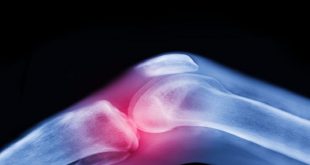

العلاج الأقوى لآلام المفاصل قبل اللجوء إلى الأدوية والجراحة (تعرف عليه)

المكلا (حضارم اليوم) متابعات تعتبر آلام المفاصل وتيبّس الركبتين وأوجاع الوركين من الشكاوى الشائعة بين كبار السن، وغالبا ما يُقبل بها كجزء طبيعي من أعراض الشيخوخة. لكن الواقع الطبي يوضح أن هذا ليس مصيرا حتميا، فالفصال العظمي — أكثر أمراض المفاصل شيوعا في العالم — يمكن الوقاية منه وعلاجه بطرق …